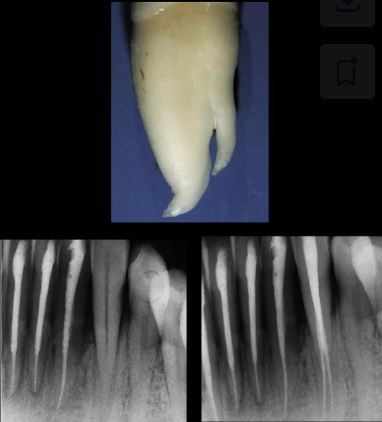

Răng cửa giữa hàm dưới

Việc điều trị răng cửa giữa cũng như răng cửa bên hàm dưới không hề dễ dàng. Trên thang độ khó, Weine xếp răng này ngay sau răng cối lớn và răng cối nhỏ hàm dưới có nhiều hơn một ống tủy. Những khó khăn liên quan đến răng này chủ yếu do sự mỏng theo chiều gần-xa khi so với chiều ngoài-trong, khiến cho việc mở rộng hoàn toàn ống tủy theo bất kỳ hướng nào trở nên rất khó khăn, nếu không muốn nói là bất khả thi. Chân răng, đôi khi có độ cong về phía xa hoặc phía lưỡi, thường chứa hai ống tủy.

Benjamin và Dawson báo cáo rằng răng cửa giữa hàm dưới có hai ống tủy trong 41,4% trường hợp, nhưng chỉ có 1,3% trường hợp có hai lỗ chóp độc lập. Theo Weine, 60% trường hợp có một ống tủy dạng dẹt theo chiều ngoài-trong, 35% có hai ống tủy hợp nhất thành một lỗ chóp chung, và 5% có hai ống tủy hoàn toàn độc lập. Do đó, có thể kết luận rằng răng cửa giữa hàm dưới nên luôn được xem xét có hai ống tủy, bởi ngay cả khi chỉ có một ống tủy, hình dạng kéo dài theo chiều ngoài-trong của nó cũng đòi hỏi phải xử lý như thể có hai ống tủy trong quá trình tạo hình lỗ mở tủy và sửa soạn nội nha.